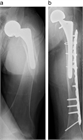

1. ⼈⼯股関節置換術(total hip arthroplasty、THA)後⾻折は種々の外⼒により発⽣するが、minor traumaによるものが多く、その発生率は一次THA後で約3.5%と報告されており、THA施行数の増加に伴い今後さらに増加すると予測される。

1. ステムの固定性が良好である場合は、ロッキングプレート、Dall-Miles cable grip system、ワイヤー、スクリューを用いた骨接合術が推奨される(推奨度1)

1. ステムに弛みを認める場合は、再置換術と骨接合術を行う(推奨度1)